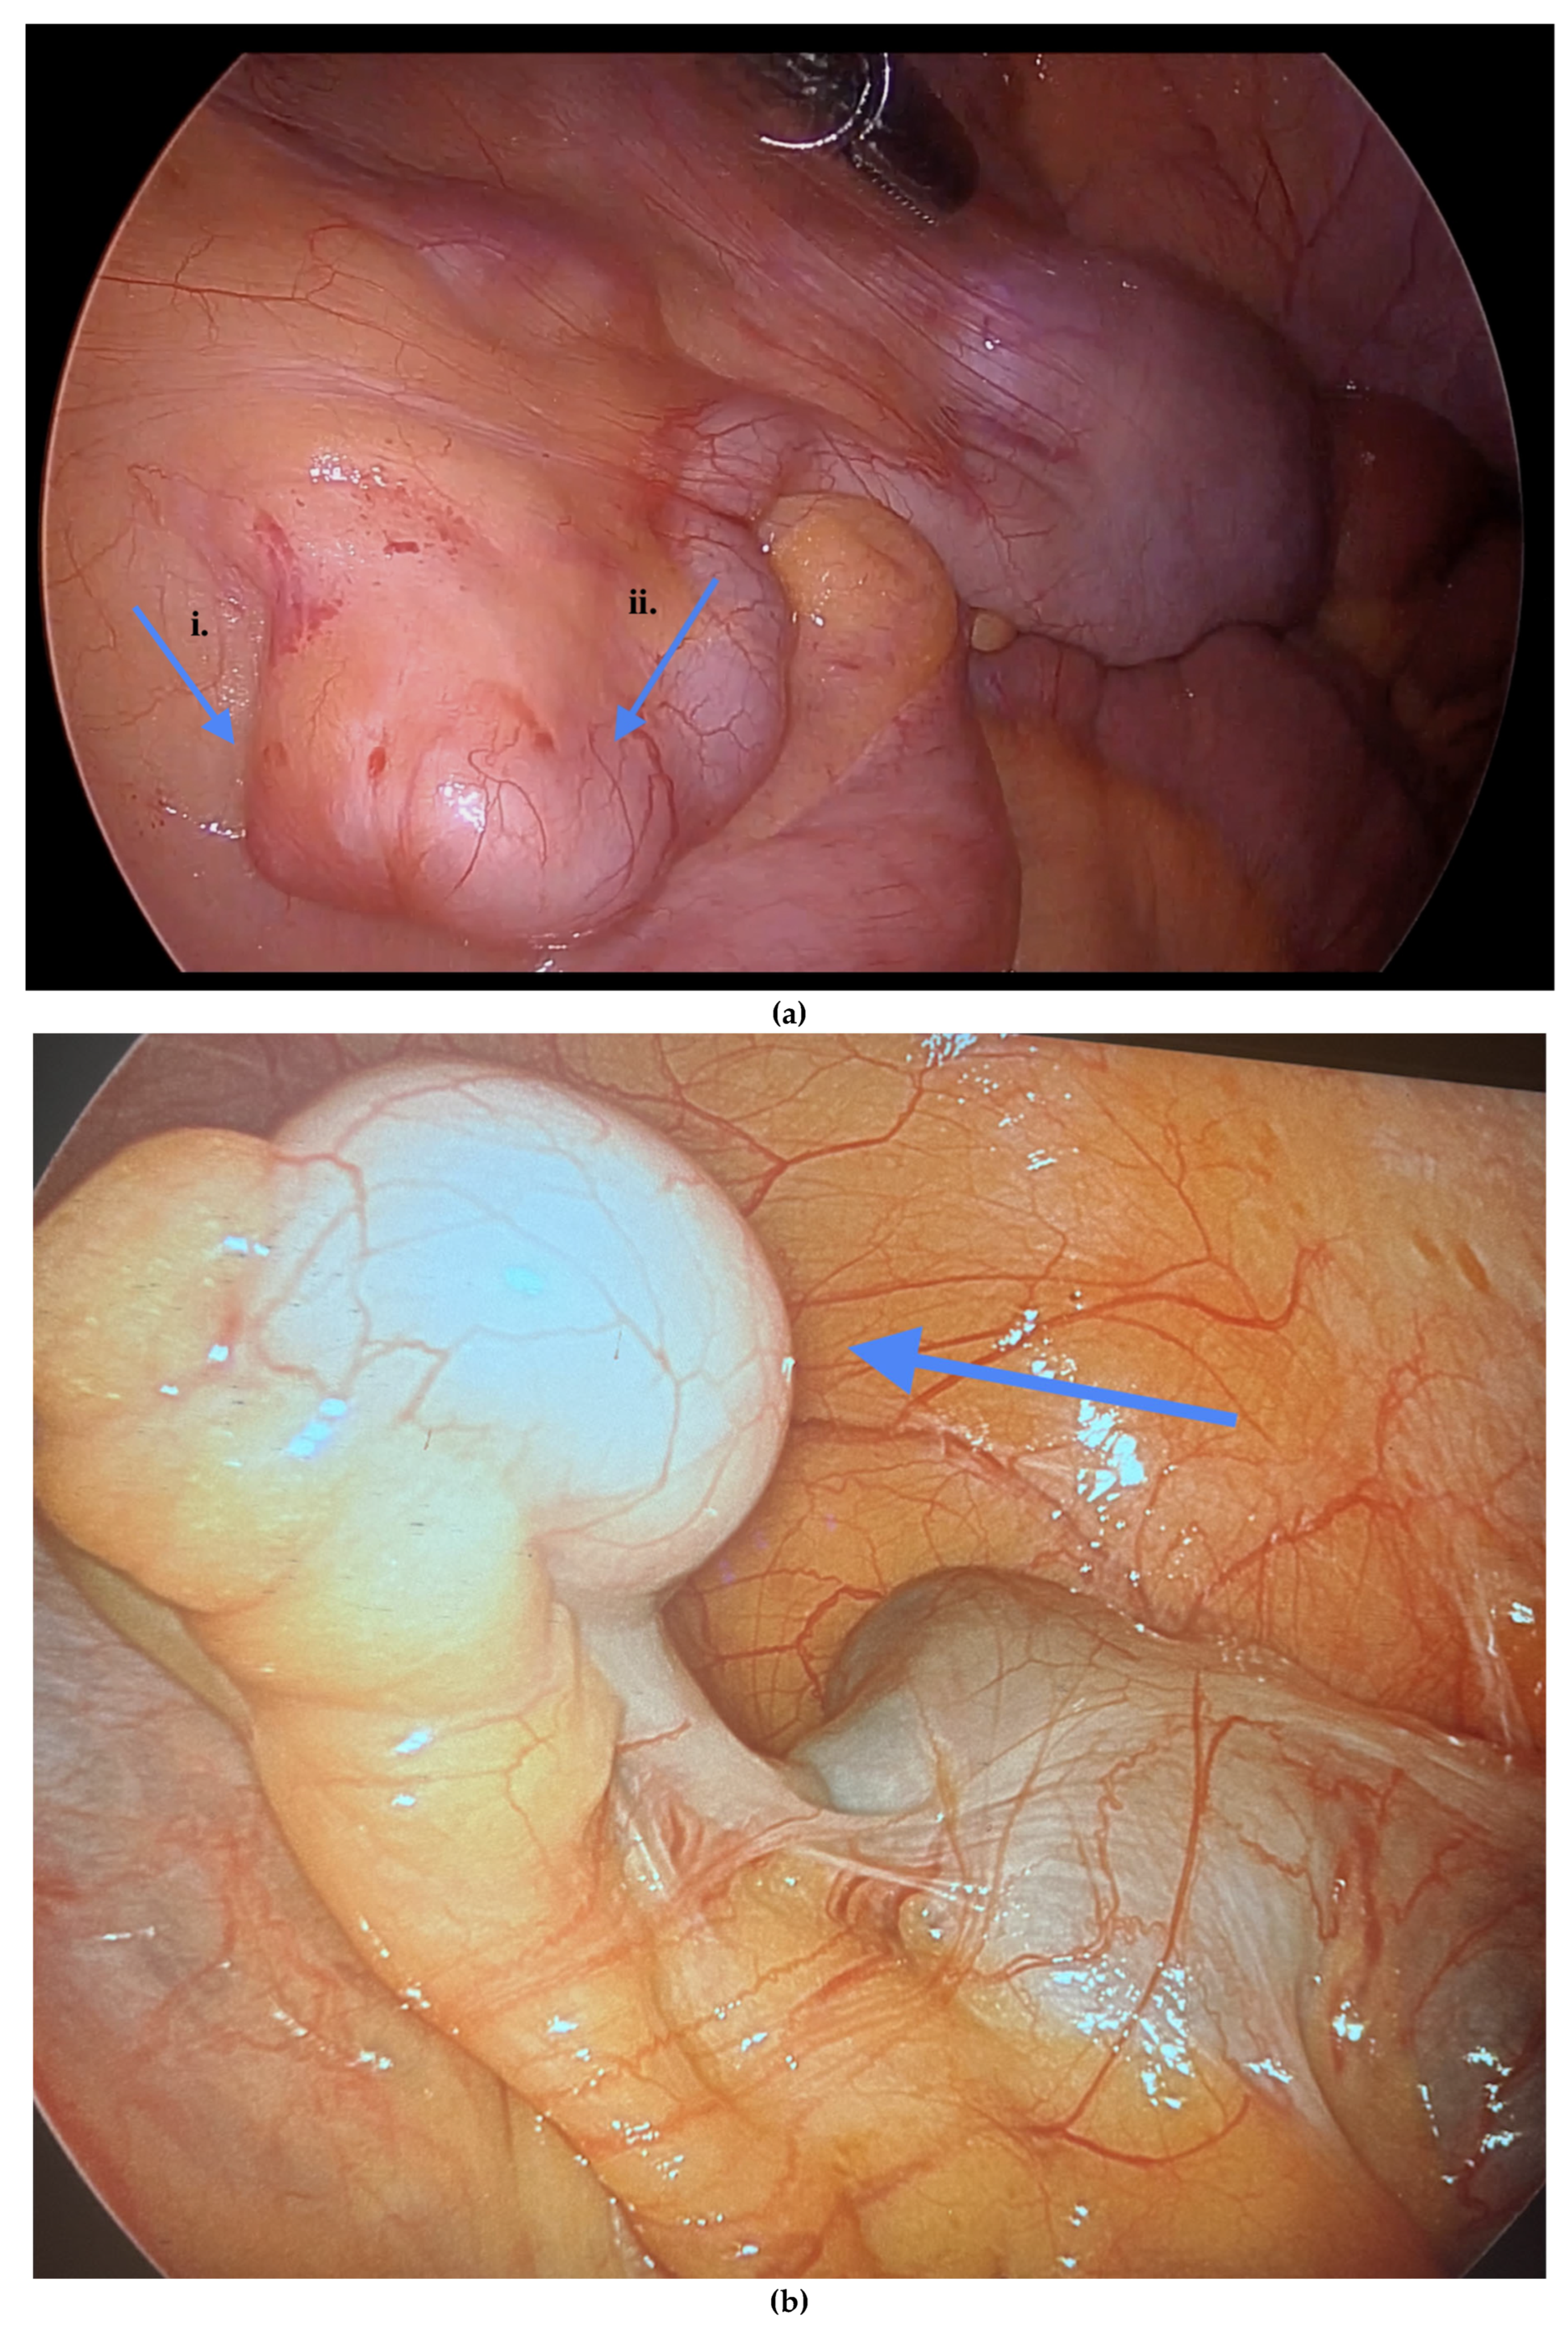

Figure 3. (a) i. Fibrous obliteration, and endometriosis at the tip. ii. Inflammation of the appendix indicating possible acute appendicitis. (b) Endometriosis on the tip of the appendix. Blue arrows indicate (a) (i) fibrous obliteration and endometriosis at the tip of the appendix, and (ii) inflammation suggesting possible acute appendicitis; and (b) endometriosis at the tip of the appendix.

Informed consent was obtained preoperatively, which included a discussion of the possibility of intraoperative appendectomy if appendiceal abnormalities were identified. During surgery, after optimal excision and ablation of endometriotic lesions, the appendix was carefully evaluated for evidence of endometriotic implants, serosal abnormalities, adhesions, fibrous obliteration, or features suggestive of acute or chronic appendicitis (Figure 1, Figure 2 and Figure 3). If abnormal findings were present, intravenous metronidazole was administered for infection prophylaxis, and a laparoscopic appendectomy was performed using the existing port sites [15]. The surgical technique included division of the mesoappendix, followed by transection and closure of the appendiceal base using a vascular stapler. The specimen was placed into a laparoscopic retrieval pouch and sent for histopathologic analysis [15,16].

Among the 216 patients with confirmed appendiceal abnormalities, many presented with more than one pathological finding (Figure 1, Figure 2 and Figure 3). Specifically, 34 patients (14.41%) had histologically confirmed appendiceal endometriosis lesions, 140 patients (59.32%) showed focal or serosal adhesions, 82 (34.75%) demonstrated fibrous obliteration, typically observed as obliteration of the appendiceal tip, and 20 (8.47%) exhibited signs of inflammation. Notably, three cases were diagnosed with neuroendocrine tumors of the appendix: one was confirmed to be malignant, while the other two were benign (Table 2).